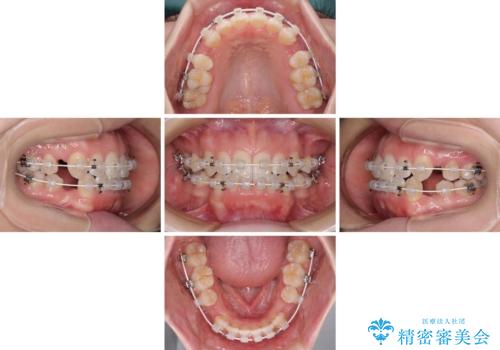

- 口元の突出感と口の閉じにくさ、前歯のデコボコを気にして来院された患者様です。

上下左右第一小臼歯4本を抜歯し、ワイヤー装置にて口元を引っ込めるよう矯正治療を行うこととしました。

骨格的に下顎骨が前方位にあるため、口元の突出感改善には限界があると思われましたが、唇の閉じにくさが改善するほど引っ込めることができました。